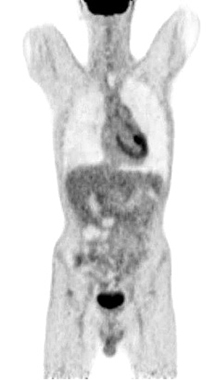

Figure 9. A normal finding of post-transplant PET/CT Scan

One year after the operation, a PET/ CT scan performed showed normal distribution of F-18 FDG and no signs of residual intraabdominal tumor (Figure 9). In the present period, the patient is disease free.